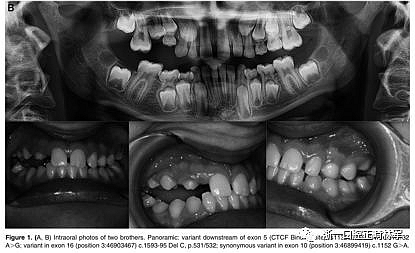

29例中有8例在PTH1R基因中發(fā)現(xiàn)雜合致病變異。表2顯示了本研究中確定的突變概況。簡言之,在8個受影響的受試者中有5個鑒定出三種錯義突變,這些受試者以前沒有根據(jù)與已發(fā)表的數(shù)據(jù)庫的比較(表3)進行描述。在兩個兄弟中鑒定出CTCF結(jié)合位點的變體(c.313×32 A.G rs113566258 SNP)(圖1A,B)。

圖1.(A,B)兩兄弟的口內(nèi)照片。全景:外顯子5的下游變體(CTCF結(jié)合位點)rs113566258 SNPc.313±32A>G; 在外顯子16中的變體(位置3:46903467)c.1593-95 Del C,p.531 / 532; 外顯子10中的同義變體(位置3:46899419)c.1152 G>A.

兄弟姐妹被診斷為I型PFE并顯示雙邊呈現(xiàn)。該變體(PTH1R基因的外顯子5的下游c.313×32 A.G)發(fā)生在與轉(zhuǎn)錄因子相互作用的調(diào)節(jié)區(qū)中。除了這種突變之外,這些兄弟還受到第二個突變的影響,這些突變對每一個都是獨特的:一個兄弟姐妹(II:1)也存在在外顯子16的基因氨基末端發(fā)生的移碼缺失,c.1593DelC ,第(Pro532Leufs *)(圖1A,B)。在另一個同胞(II:3)中,鑒定出在蛋白質(zhì)氨基酸序列水平不引起變異的外顯子,c.1152GA(rs200475872;圖1A,B)中的同義變體,但涉及改變含氮堿。基于計算機分析,這種改變可能會影響mRNA的折疊并影響其半衰期和蛋白質(zhì)生產(chǎn)。在這個患者樣本中,在一個孤立的病例中發(fā)現(xiàn)了同樣的同義變體c.1152G.A,由于PFE而具有嚴(yán)重的開合(圖2)。

本研究中確定的低咬合的臨床特征與PFE基于基因診斷和萌出障礙診斷標(biāo)準(zhǔn)的應(yīng)用相一致。對特定相關(guān)牙科特征的仔細(xì)臨床檢查包括以下內(nèi)容:至少一顆牙包括低咬合,局限于后部區(qū)域,單側(cè)(38%;圖1A)和雙側(cè)呈現(xiàn)(35%;圖1B和2),至少有一個暫時性后牙(48%暫時;圖1A,B和3A; 55%永久性,圖3B)。此外,觀察到牙面特征如下:由于受影響側(cè)的側(cè)向開放咬傷的嚴(yán)重程度而引起的垂直骨骼不對稱(35%;圖1A,B和圖3A,B);由下頜骨側(cè)向偏離組成的面部不對稱(圖1A,B和圖2;表4)。這種不對稱在單側(cè)開合患者中更為明顯。進一步發(fā)現(xiàn)受影響的患者與先前報道的患者存在上頜骨收縮和III類牙齒/骨骼關(guān)系(28%;圖1A,B和圖2)。至少有一例患者出現(xiàn)了相對于9名患者的低咬合。表4總結(jié)了PTH1R的表型結(jié)果和相關(guān)的突變分析(N = 8)。